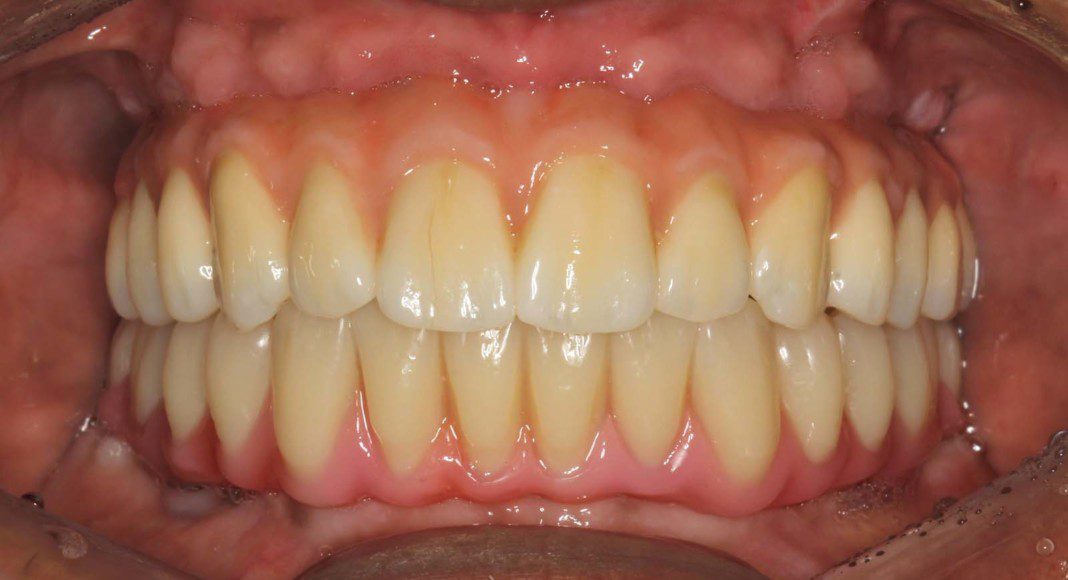

Lower titanium/ acrylic (titanium skeleton/ acrylic wrapped and retained to the titanium) bridge in mouth. Frontal view.

Lower prosthesis was removed at the patient’s request. He believed he had something “stuck”. What he was feeling was healthy tissue around an implant. Note how much healthier (pinker) the tissues are with the polished titanium touching them. Frontal view.

This treatment is as good as humans can do in 2023. Because we staged the treatment for maximum patient benefit, waited the appropriate time between segments, sweated every detail, completed each step as perfectly as possible, honored the patient’s wishes, added our own expertise and advice, and didn’t cut corners, the patient received a flawless result. This is the type of treatment and outcome that every dentist and dental specialist would request if they needed full mouth implant reconstruction. So, why are we one of very few offices that render and advocate this treatment? Something to ponder in your free time!